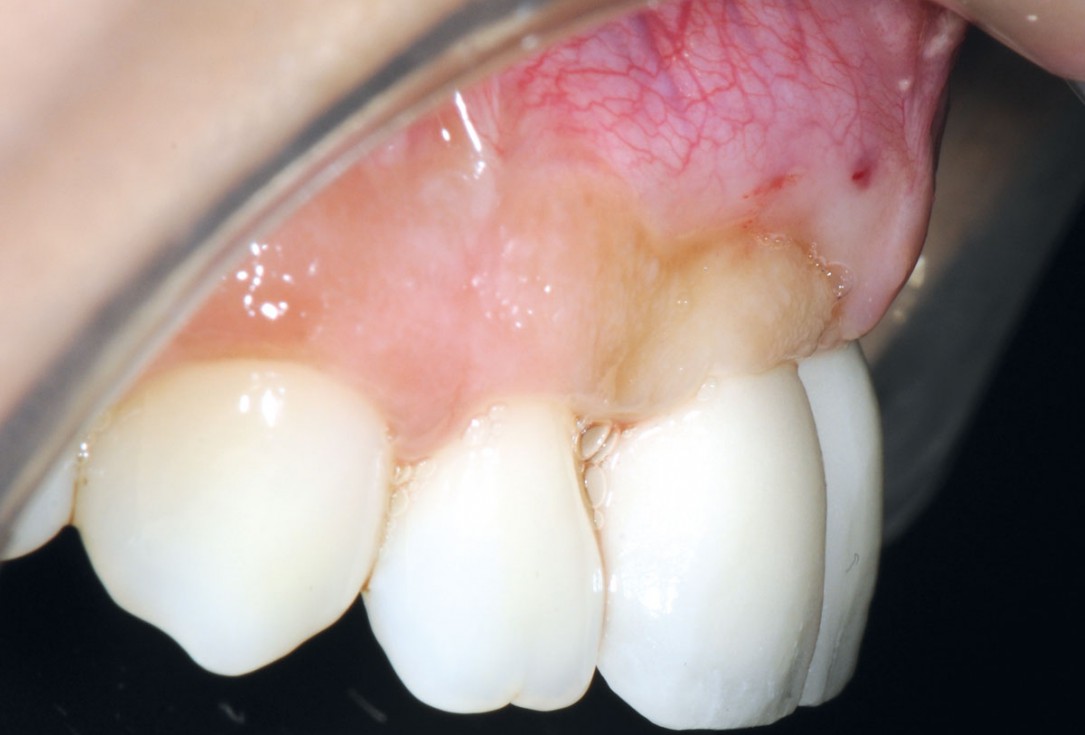

20/26 - 6 weeks post-op: sutures were removedBone augmentation in aesthetic zone with maxgraft® bonering - Dr. A. Patel